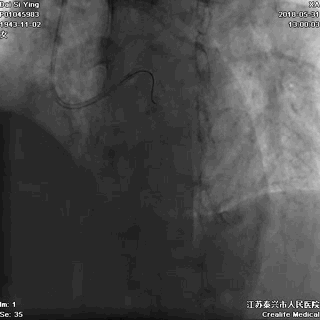

一名姓张的男子,51岁,胸痛2小时后到家附近的卫生院就诊,心电图提示“急性下壁心肌梗死”“室性早搏”。

医生建议他们赶紧乘坐120救护车赶往医院抢救,家人不听劝告,自己开私家车送院,途中病人突然发生室颤,不幸死亡。  急性心肌梗死、室性早搏

记住:心梗发生后,一旦再出现恶性心律失常,患者很难自救。120救护车上有专业的急救设备和经验丰富的急救人员,是送院途中的生命保障。